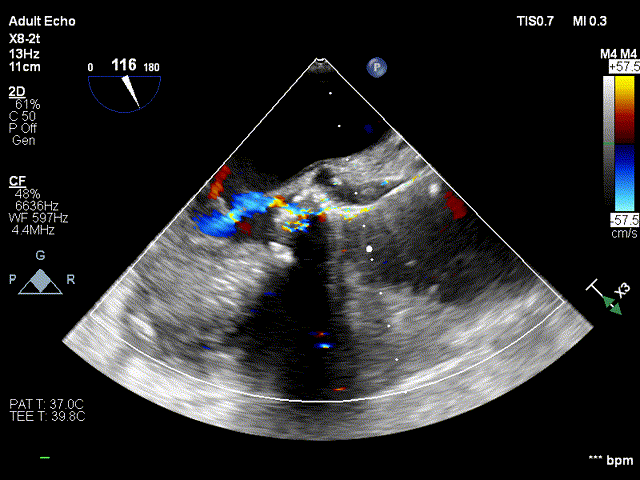

术前超声

术前超声-短轴切面

术前超声-长轴切面

术后超声:

术后超声-短轴切面

术后超声-长轴切面

术前跨瓣压差

术后跨瓣压差

随着TAVR技术在国内的普及,主动脉瓣狭窄患者有了更多的治疗选择。本例病人为主动脉瓣重度狭窄伴轻度反流,手术指征明确,患者明确拒绝外科手术,术前解剖形态评估适宜行TAVR手术,有TAVR手术指征。经罗骏、崔凯教授团队的综合评估,结合心内科、心外科、超声等多学科团队的讨论意见,最终决定为患者施行TAVR手术治疗。手术过程中,TaurusElite经导管主动脉瓣输送系统在保持回收性能稳定的同时兼具优异的柔顺性,顺利完成过弓、跨瓣操作。其次,针对本例患者钙化较重、瓣叶局部粘连的特点,TaurusElite瓣膜高密度流入端设计提供了足够的径向支撑力,保证了瓣膜的锚定力;低密度流出端的设计也兼具柔顺性,能帮助术者更好的完成过弓与跨瓣操作。此外,TaurusElite瓣膜内外双裙边设计能有效减少瓣周漏,适度的收腰既能保证足够的有效瓣口面积,又降低了冠脉阻挡风险。最后,面对临床复杂的解剖结构特点,瓣膜释放过程中可能出现瓣膜下滑或上跳的风险,增加了术中释放瓣膜的难度;而TaurusElite瓣膜系统具有多次原位回收、回收后可重新跨瓣等设计特点,让术者释放过程中更有信心,能降低手术风险,减少并发症的产生,从而让患者得到更好的预后。本例患者术中的情况验证了术前CT分析的准确性,最终瓣膜释放位置良好,冠脉血流灌注正常,术后压差明显降低,术后跨瓣压差从101mmHg降至2mmHg,仅有微少量瓣周漏。术后病人恢复良好,各项生命体征平稳,手术效果十分优异。